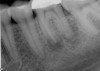

Figure 4 through Figure 10 depict several teeth that have conservative accesses while still allowing the clinician to adequately instrument and clean each tooth to achieve effective root canal therapy. The success of these cases still hinges on the proper cleaning and shaping of the root canal system, and while conservative accesses are desirable, too small of an access can lead to missed canals, poor instrumentation, improper cleaning, and, ultimately, a failed procedure.

Fig 4. Endodontic therapy on molar with four canals.

Figure 4

Fig 5. Same tooth as shown in Figure 4 allows for visualization of tiny access despite having obturated four canals.

Figure 5